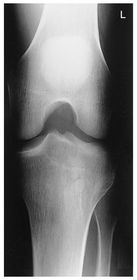

A. medial and lateral intercondylar tubercles B. lateral epicondyle femur C. lateral condyle femur D. lateral condyle tibia E. articular facets tibia (tibial plateau) F. medial condyle tibia G. medial condyle femur H. medial epicondyle femur I. patella